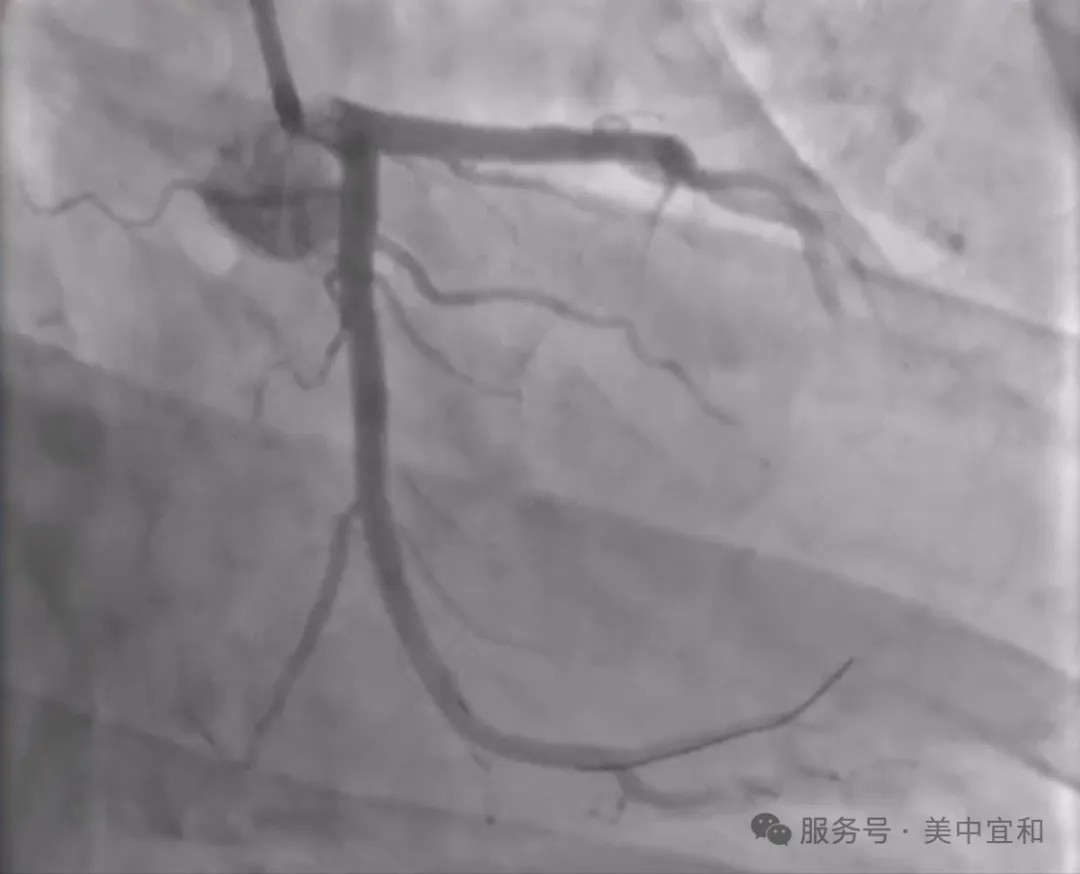

冠脈造(zao)影下汪先(xian)生(sheng)的(de)血筦(guan)影像比想象中(zhong)還要“糟糕”:左冠回旋支(LCX)中(zhong)段長(zhang)段高(gao)度狹窄,最重(zhong)處達 90%,屬于(yu)高(gao)危複雜病變。長(zhang)段狹窄意味着需要精(jīng)準覆蓋(gai)病變全程(cheng),且容易出現(xian)支架貼壁不良、血筦(guan)夾層等(deng)風險;90% 的(de)重(zhong)度狹窄則要求手術(shù)過(guo)程(cheng)中(zhong)對血流的(de)保護極爲(wei)嚴格,稍有(yǒu)不慎就可(kě)能(néng)引髮(fa)心肌缺血甚至梗死。

(冠脈造(zao)影可(kě)見汪先(xian)生(sheng)回旋支中(zhong)段約90%重(zhong)度狹窄)